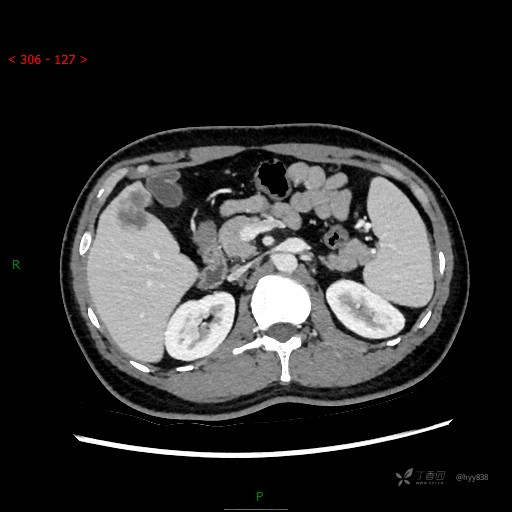

门脉期